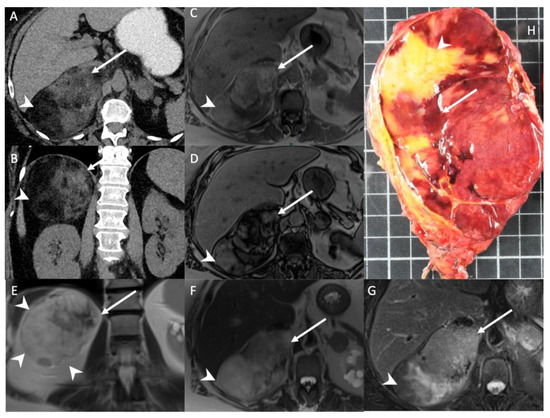

- Kedra, A.; Dohan, A.; Gaujoux, S.; Sibony, M.; Jouinot, A.; Assie, G.; Groussin Rouiller, L.; Libe, R.; Bertherat, J.; Soyer, P.; et al. Preoperative Detection of Liver Involvement by Right-Sided Adrenocortical Carcinoma Using CT and MRI. Cancers (Basel) 2021, 13, 1603. [Google Scholar] [CrossRef] [PubMed]

9.1. Computed Tomography

9.2. Magnetic Resonance Imaging